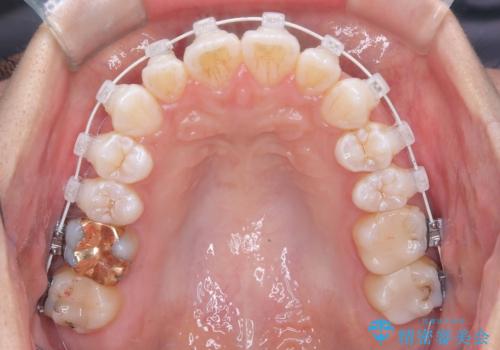

治療は、白いコーティングが施されたワイヤーを使用した審美性の高い装置にて行っています。

本症例では、治療の途中で**バイトアップ(咬み合わせを一時的に挙上する処置)**を行い、

上下の歯が干渉しない環境を作りながら、捻転や叢生の改善を進めました。

装置には、ワイヤーに白いコーティングが施された審美性の高いワイヤー矯正装置を使用し、

治療中も目立ちにくい配慮を行いました。